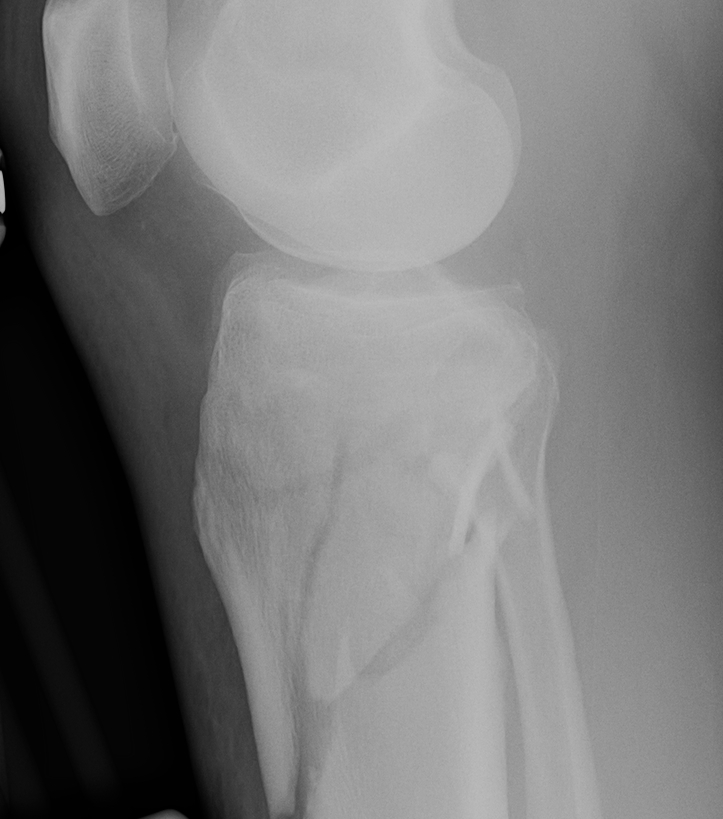

Schatzker Classification

I. Lateral Spilt

- seen in young patient

- lateral meniscus can be incarcerated in fracture

II. Lateral Split Depression

- often seen in young patients with high energy injuries

- vary in severity

III. Lateral Depression

- central depression usually seen in elderly

- have to create lateral cortical window in order to elevate fragment

IV. Medial plateau & intercondylar eminence

- high velocity injury associated with ACL / LCL / CPN injury

- can be low injury / osteoporotic and often unreconstructable

V. Bi-condylar + intact metaphysis

- unstable

- requires ORIF

VI. Bi-condylar + metaphyseal fracture

- fracture separating metaphysis from diaphysis

- highest incidence of vascular injury